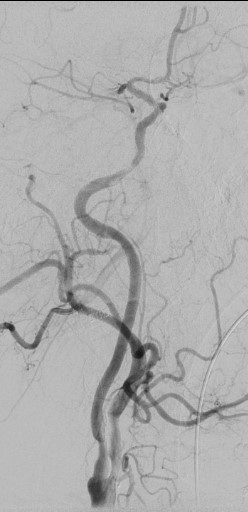

13:00 Больной подан в рентгеноперационную, выполнена церебральная ангиография: Ангиографические признаки атеросклеротического процесса брахиоцефальных артерий, тромботической окклюзии правой ВСА(Рис1), окклюзия левых ВСА(Рис3) и ПА(Рис2).

Рис4 заполнение системы левой ВСА через левую заднюю соединительную артерию.

рис. 3 рис. 4